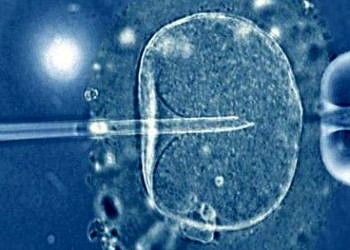

Tüp bebek yöntemiyle dünyaya gelen insanların ömürleri daha mı kısa?

DevamıTüp bebek yöntemi doğal yollardan bebek sahibi olamayanlar için laboratuar ortamında oluşturulan döllenme işlemidir. Son yıllarda gelişen tıbbi teknolojiler sayesinde tüp bebek tedavisinde başarı oranlarının çok yükselmiştir.